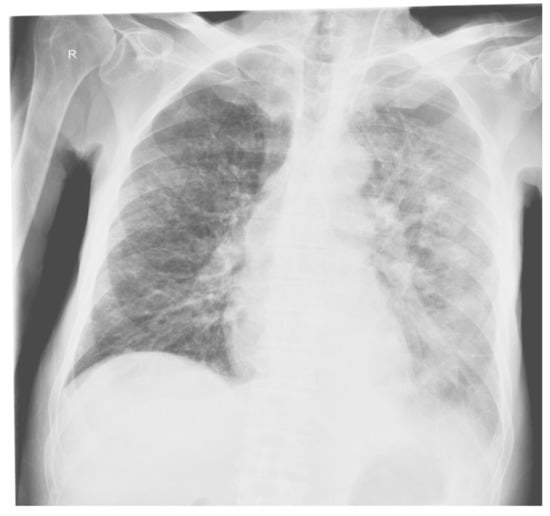

The pulmonary radiological examination performed 30 days after hospitalization revealed: veiling of the left lung field, bilateral accentuated lung drawing, with alveolar condensation processes, predominantly left lung; opacification of the left cost-diaphragmatic sinus, left apical pulmonary hypertransparency; increased projection area of the left hilum; mitral configured cord (Figure 9).

Figure 9. Patient’s X-ray (performed 30 days after hospitalization): bilateral accentuated lung drawing, with alveolar condensation processes, predominantly left lung; opacification of the left cost-diaphragmatic sinus, left apical pulmonary hypertransparency. ‘R’= right.